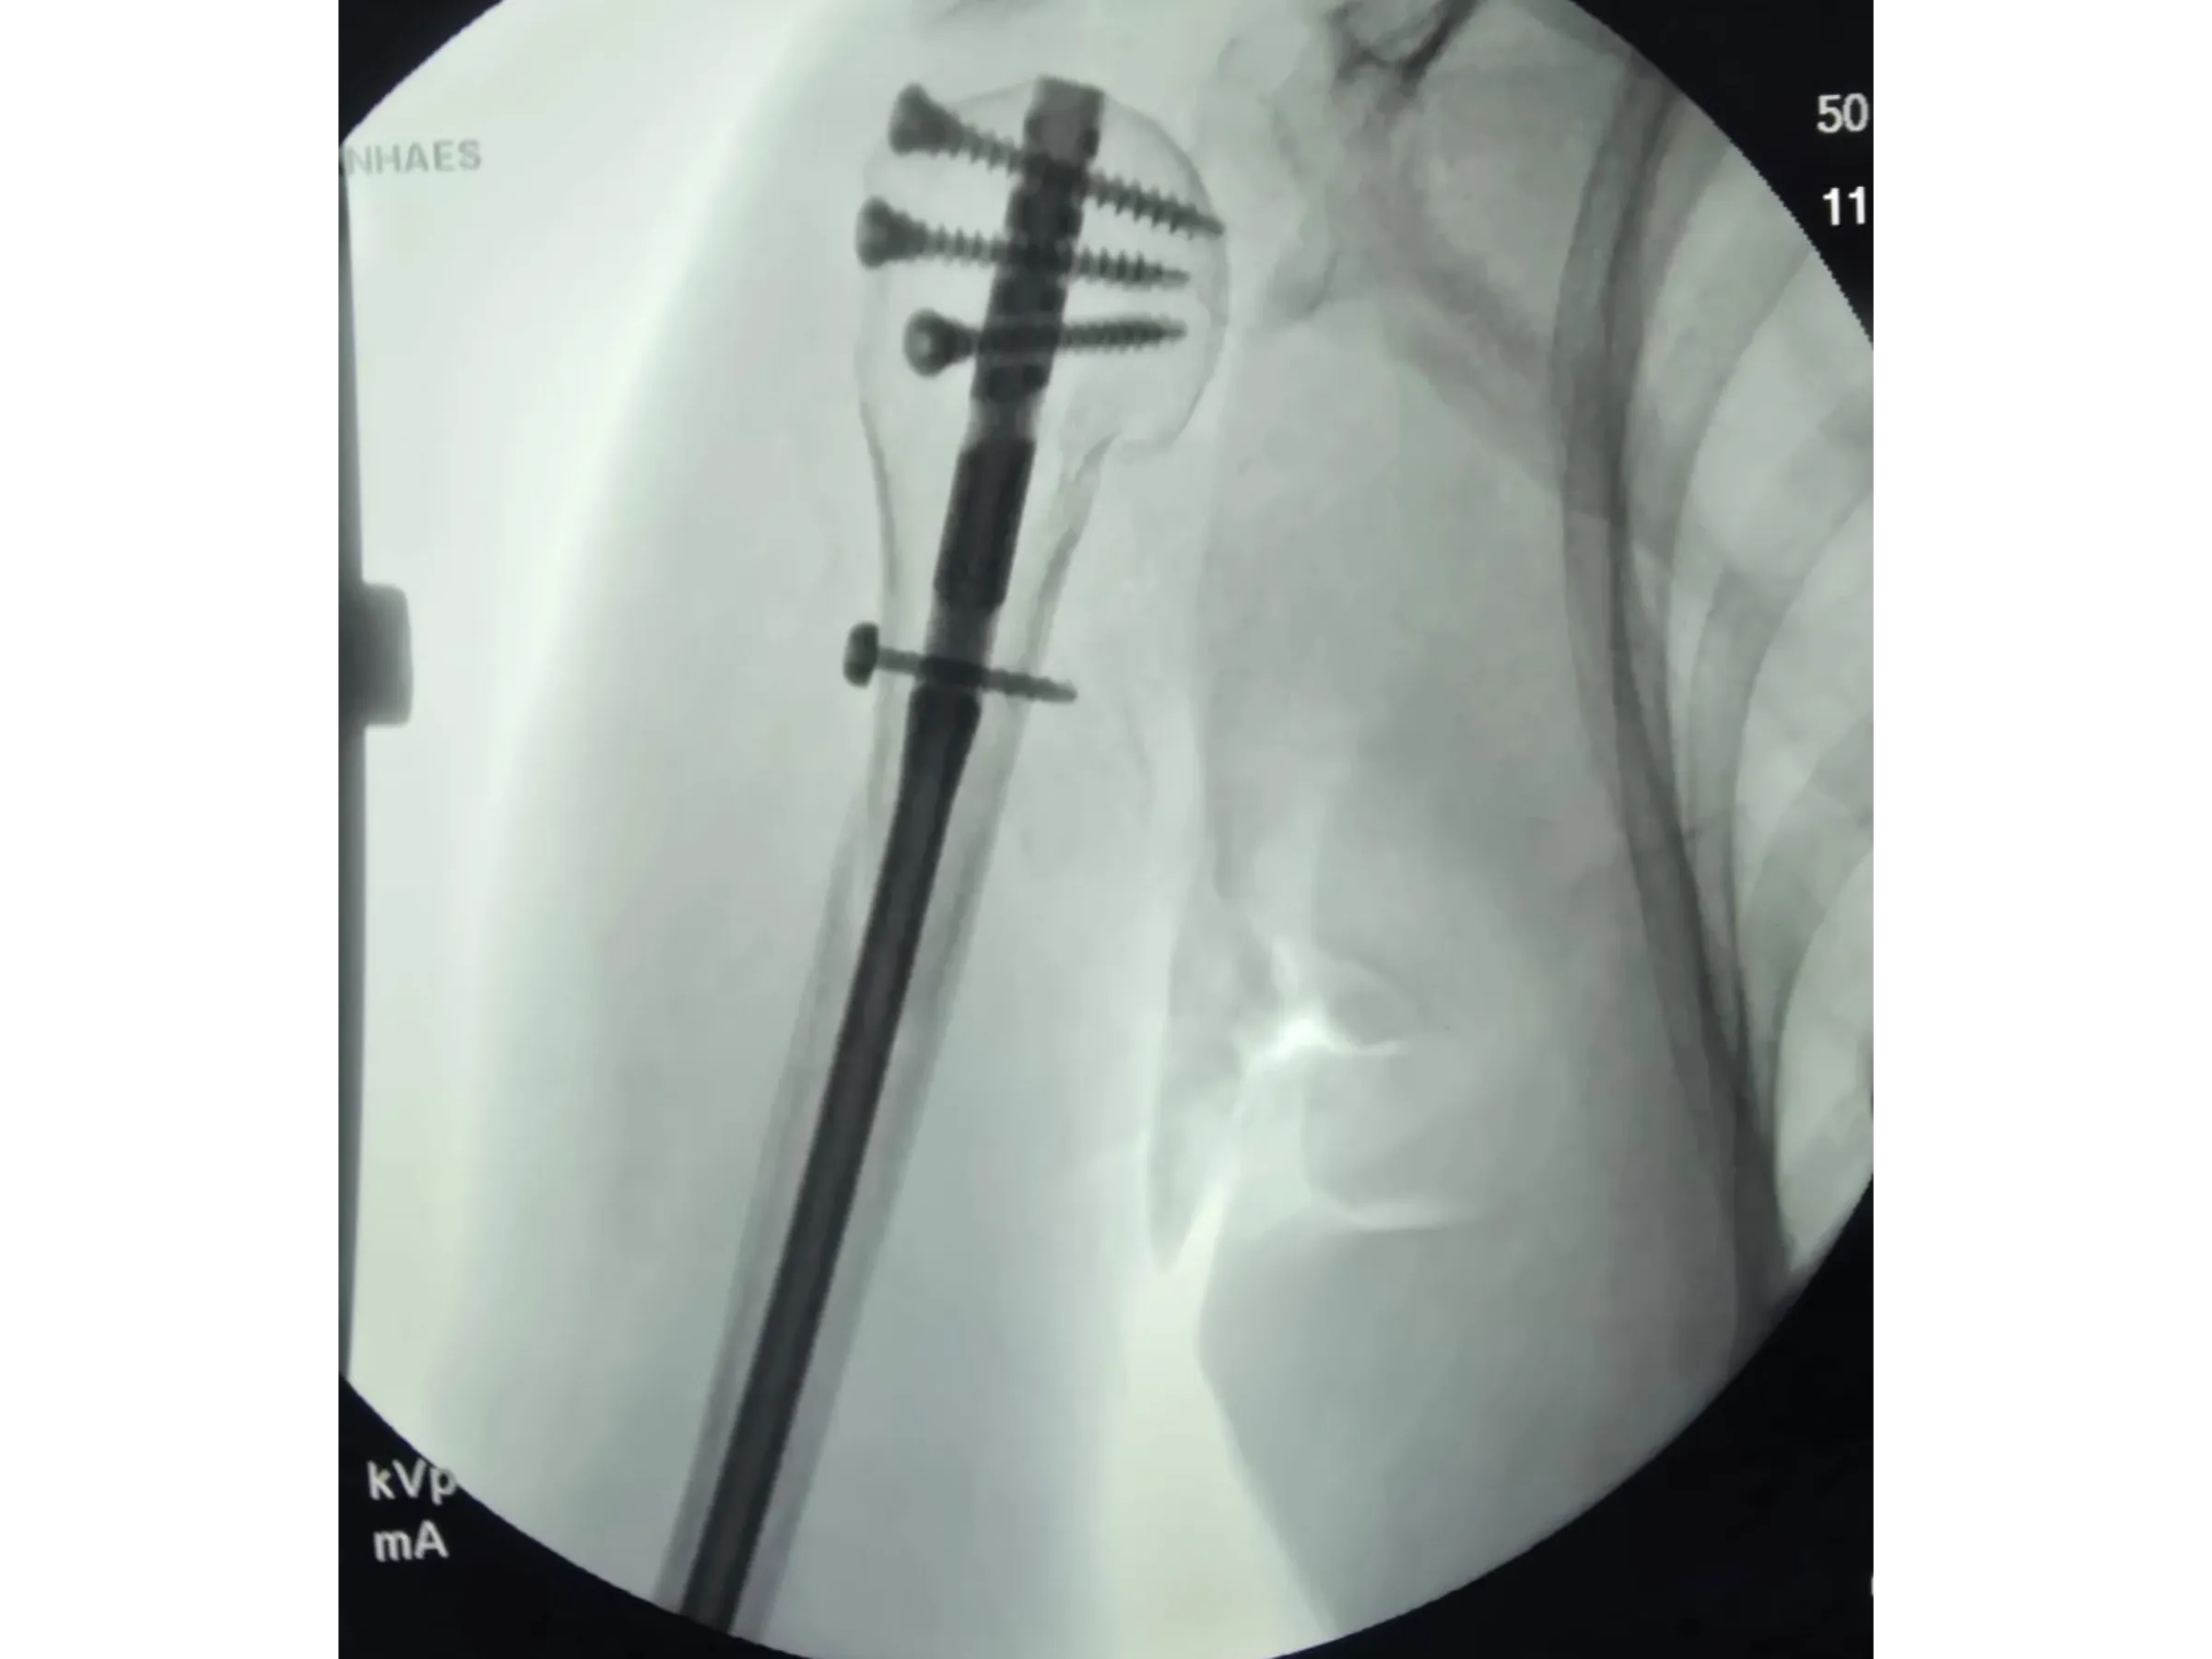

- Insertion of a long intramedullary rod with proximal and distal locking.

- Stable Intramedullary Fixation: Insertion of a long rod with multiple locking screws, including metaphyseal screws.

- Rigorous Fluoroscopic Control: Anteroposterior and lateral images to ensure parallelism and precision of the implants.